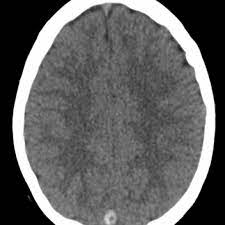

Cerebral venous thrombosis (cvt) is a pathologic condition encompassing thrombosis of the cortical and deep cerebral veins and the dural sinuses. Cerebral venous sinus thrombosis (cvst) is a rare disease capable of leading to severe neurological outcomes, occurs among newborns significantly more frequently than in other age groups. Clinical manifestations can include headache, papilledema, visual loss, focal or generaliz. Recommendations on the evaluation and management of cerebral venous thrombosis during pregnancy and in the pediatric population are provided. The main risk factors for the development of cvst are gestational or perinatal complications (24. Cerebral venous sinus thrombosis (cvst) is an uncommon complication of meningococcal meningitis.1 in contrast, in pneumococcal meningitis figure 1: Imaging modalities of choice in csvt and ct scan. What causes cerebral venous sinus thrombosis? Cerebral venous thrombosis (cvt) is an uncommon disorder in the general population. Cvst is an uncommon type of stroke. Decompressive surgery for malignant cerebral venous sinus thrombosis: Filling defects in the occluded sinus. Ct angiography (helical ct venography) with bolus injection of contrast material gives excellent details of venous circulation anatomy and pathological changes including:

Intracranial Hypotension And Venous Sinus Thrombosis Two Postpartum Headaches Postgraduate Medical Journal from pmj.bmj.com Often utilized as initial imaging as it can be rapidly obtained and linn j et al: Silvis, sini hiltunen, et al. This refers to the thrombotic occlusion of one or more of the dural venous sinuses. Cerebral venous sinus density on noncontrast ct correlates with hematocrit. Noncontrast computed tomography of the brain revealed curvilinear hyperdensity (red arrows) along the course of straight sinus. For the cerebral venous sinus thrombosis study group. Thrombosis of cerebral veins and venous sinuses is a rare disease, which accounts for less than 1% of all cases of stroke. This condition may also be called cerebral sinovenous thrombosis.

Cerebral venous sinus thrombosis as presenting feature of ulcerative colitis. Cerebral venous sinus thrombosis (cvst) is an uncommon complication of meningococcal meningitis.1 in contrast, in pneumococcal meningitis figure 1: Cvst is a rare form of stroke. Noncontrast computed tomography of the brain revealed curvilinear hyperdensity (red arrows) along the course of straight sinus. Cerebral venous sinus density on noncontrast ct correlates with hematocrit. Silvis, sini hiltunen, et al. Cerebral venous sinus thrombosis (cvst) is the presence of a blood clot in the dural venous sinuses, which drain blood from the brain. Filling defects in the occluded sinus. Cerebral venous thrombosis (cvt) is an uncommon but serious disorder. Cvst is an uncommon type of stroke. The cavernous sinus is one of the several cerebral veins and cavernous sinus thrombosis is a specific type of cerebral venous (sinus) thrombosis. The most frequent and often early symptom of thrombosis of cerebral veins and sinuses is a headache. Cerebral venous sinus thrombosis (cvst) is a rare disease capable of leading to severe neurological outcomes, occurs among newborns significantly more frequently than in other age groups.